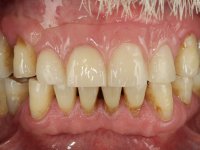

Paciente do sexo masculino, com 64 anos de idade, não fumador, recorreu á minha consulta após traumatismo do sector anterior. Os dentes 2.1 e 2.2 apresentavam extensas fraturas infra ósseas. Os dentes 1.2 e 1.1 apresentavam-se ferulizados com uma resina composta na zona inter-proximal. O dente 1.1 apresentava um tratamento endodôntico sofrível e um poste intra-radicular. O dente 1.2 estava vital e tinha uma extensa restauração da resina composta. Estando ferulizados, não foi possível avaliar o grau de mobilidade dentária de cada um dos dentes, mas o conjunto não tinha mobilidade. Após exame clínico e Imagiológico conclui-se que as raízes dos dentes 2.1 e 2.2 tinham extração indicada. O paciente estava reabilitado provisoriamente com uma prótese removível esquelética com 3 dentes. Apresentava algum comprometimento periodontal e os dentes mostravam as superfícies oclusais e incisais desgastadas. Higiene oral razoável.